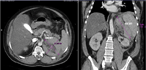

An incredibly dilated Wirsung mimicking a sero-cystic neoplasm of the pancreatic head

Contardo Vergani and others

Journal of Surgical Case Reports, Volume 2018, Issue 6, June 2018, rjy122, https://doi.org/10.1093/jscr/rjy122